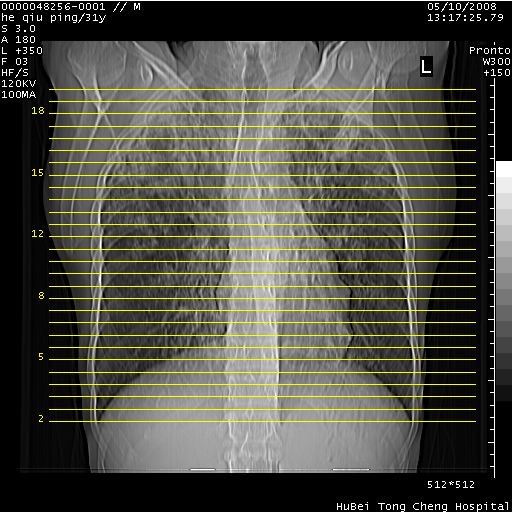

标题: CT13402:M,31Y。肺结核伴空洞形成? [打印本页]

标题: CT13402:M,31Y。肺结核伴空洞形成?

咳嗽半月余,消瘦体质,呼吸音弱。无其他病史。cr:肺转移瘤待。